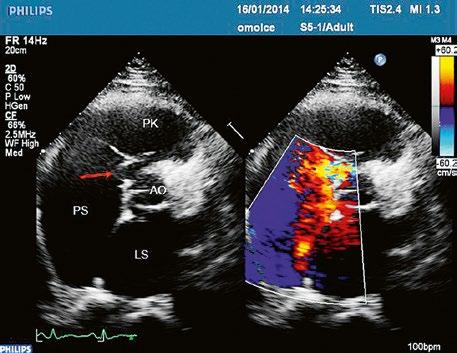

Supravalvární pulmonální stenóza a stenózy větví plicnice bývají součástí komplexních VSV (např. Fallotovy tetralogie) nebo syndromů (Williamsův syndrom, syndrom Noonanové, syndrom vrozené rubeoly, Alagillův syndrom aj.) (Obr. 45.39). Získané stenózy větví plicnice, ale i úplný uzávěr větve plicnice můžeme vidět po spojkových operacích podle BlalockaTaussigové (Obr. 45.40, Obr. 45.41). Pro zobrazení supravalvárních a periferních stenóz plicnice je optimální CT angiografie (Obr. 45.40, Obr. 45.41, Obr. 45.42, Obr. 45.43).

Obr. 45.39 TEE, valvární a supravalvární stenóza plicnice blízko nad chlopní, označena křížky. Valvární stenóza s domingem chlopně označena šipkou. AP – kmen plicnice za stenózou, RVOT – výtokový trakt pravé komory